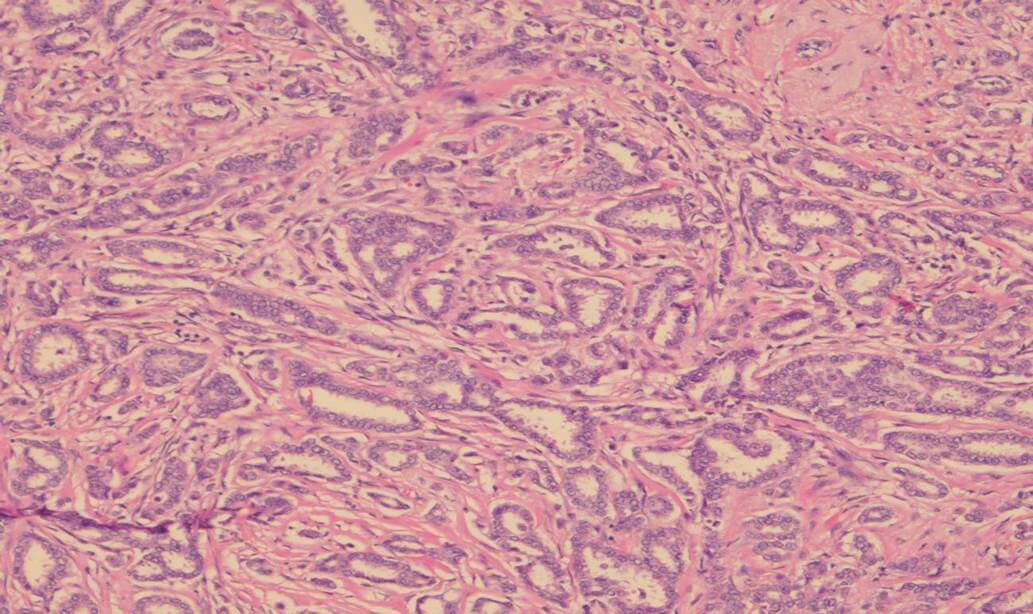

Invasive carcinoma is most commonly ductal carcinoma of no special type, with invasive lobular carcinoma the next most common. Invasive lobular carcinoma may show more extensive disease than appreciated clinically, or on imaging pre-operatively, and it is useful for this identification to assist with planning surgery. Tumour grade is a measure of tumour differentiation and is an important prognostic variable that influences decisions about additional treatment such as chemotherapy. Grading takes into account the ability of the tumour to make glands, the degree of nuclear pleomorphism and the proliferative rate measured by counting mitoses (Figure 1 – grade 1 invasive carcinoma, Figure 2 – grade 3 invasive carcinoma).

This image depicts grade 1 invasive carcinoma. Professional medical imaging for clinical reference and educational purposes. [umbracoNodeId=9796]

Figure 1: Grade 1 invasive carcinoma